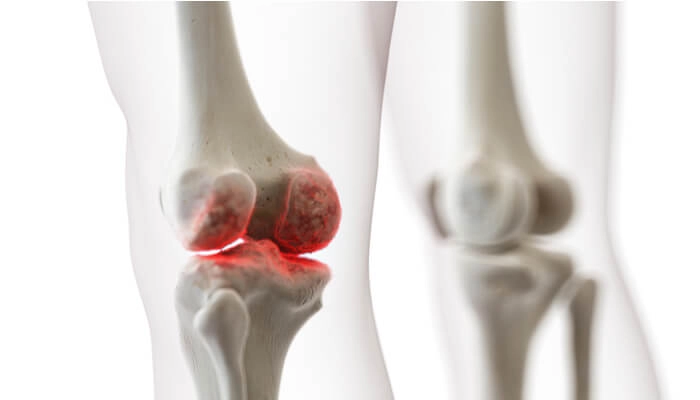

عفونت زانو یکی از جدیترین اختلالات مفصلی است که در صورت عدم درمان بهموقع میتواند منجر به آسیبهای دائمی مفصل، تخریب غضروف و حتی گسترش عفونت به سایر بخشهای بدن شود. این مشکل میتواند به دلایل مختلفی مانند ورود میکروب از طریق خون، آسیبدیدگی یا پس از جراحی در ناحیه زانو بروز کند. شناخت سریع علائم، تشخیص درست و درمان فوری نقش حیاتی در پیشگیری از عوارض جدی دارد.

عفونت زانو زمانی رخ میدهد که باکتری، ویروس یا قارچ وارد فضای مفصلی زانو شود. این حالت با نامهای پزشکی آرتریت سپتیک یا عفونت مفصل زانو شناخته میشود. این عفونت معمولاً با التهاب شدید، درد، تورم و گاهی تب همراه است و نیازمند درمان اورژانسی است.

تشخیص عفونت مفصل زانو چگونه انجام میشود؟

برای تشخیص دقیق عفونت، پزشک از مجموعهای از روشها استفاده میکند:

- تصویربرداری مانند MRI یا سونوگرافی برای بررسی میزان آسیب مفصل

عوارض عدم درمان بهموقع عفونت زانو

درمان نکردن بهموقع عفونت زانو میتواند منجر به:

- تخریب دائمی مفصل